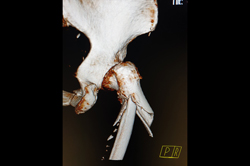

Metarsals with dislocations Lisfranc